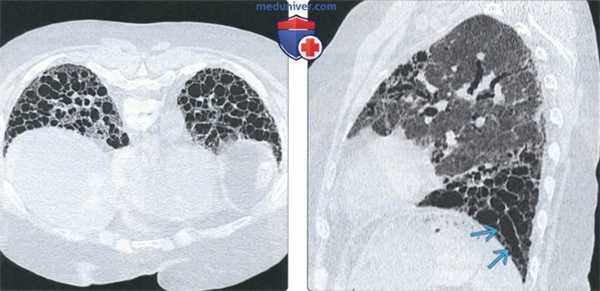

(Слева) На аксиальной КТВР у пациента с прогрессирующим системным склерозом и НСИП в базальных отделах легких определяются участки «матового стекла» и кистовидные структуры, сопоставимые с бронхоэктазами.

(Справа) На сагиттальной КТВР у этого же пациента визуализируются кистовидные структуры, намного больше напоминающие бронхоэктазы, чем «сотовое легкое». Бронхоэктазы (вне зависимости от тяжести интерстициального заболевания легких) часто встречаются у пациентов с прогрессирующим системным склерозом.